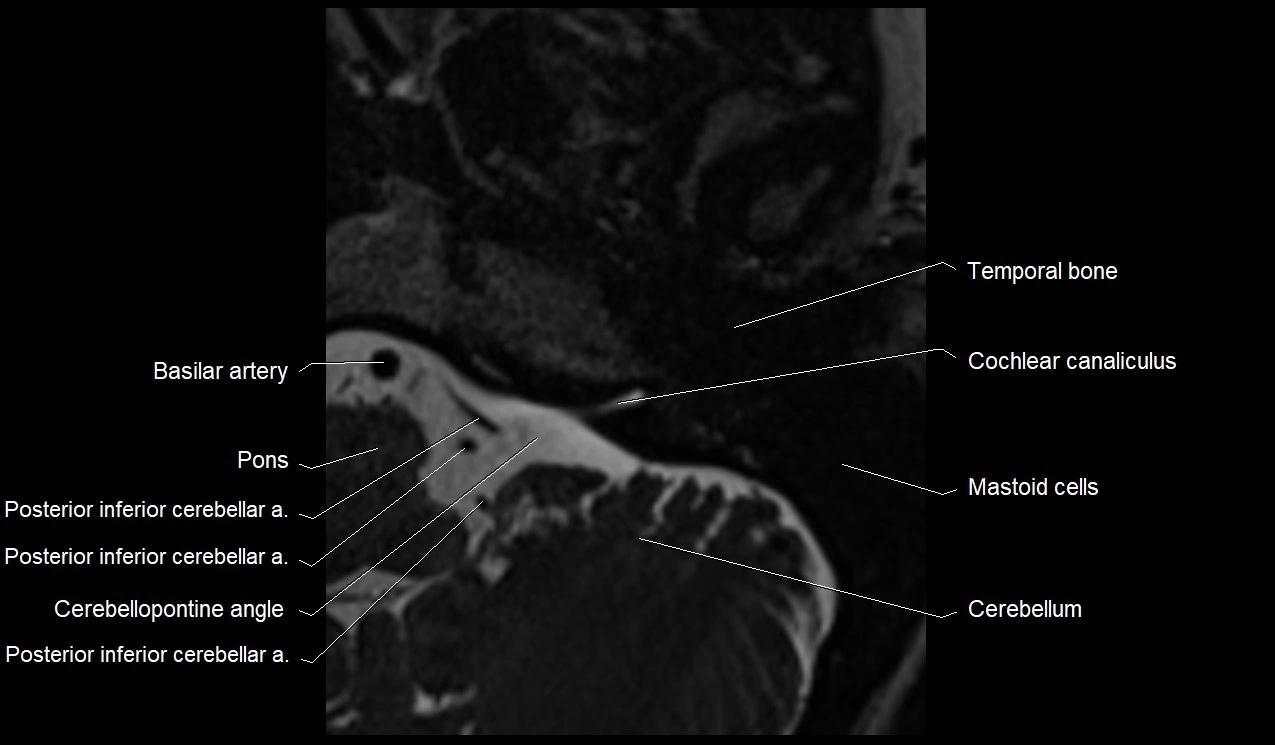

MRI Appearance

• The abducens nerve is a small, thin, linear structure

• Best visualized on high-resolution T2-weighted 3D MRI sequences (e.g., FIESTA or CISS)

• Seen as a hypointense (dark) line running from the brainstem at the pontomedullary junction, traversing the prepontine cistern, and entering Dorello’s canal under the petrosphenoidal ligament, then into the cavernous sinus, and finally the orbit

• May be challenging to visualize in standard MRI due to its small size

• Pathology may be inferred by absence, displacement, or enhancement of the nerve